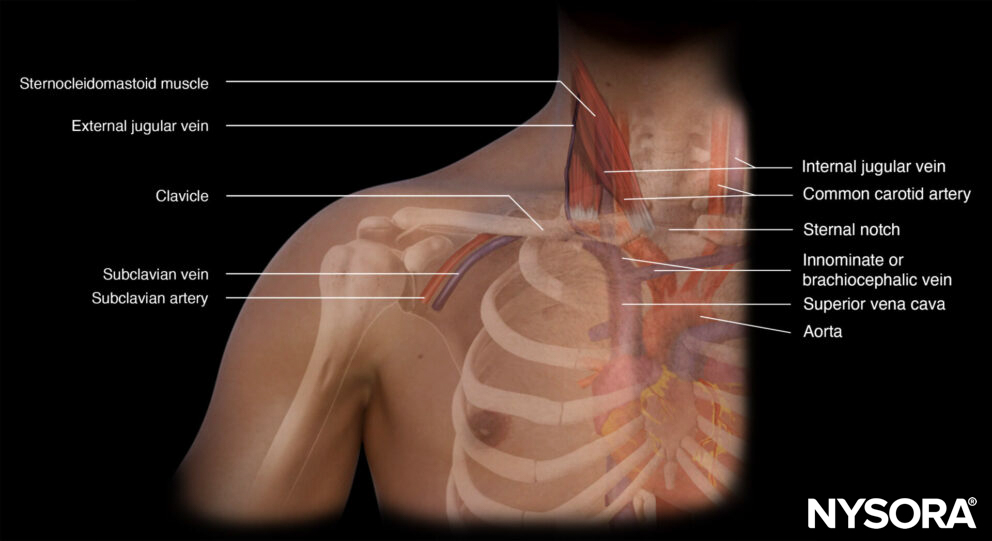

Functional anatomy

Anatomy of the subclavian vein.